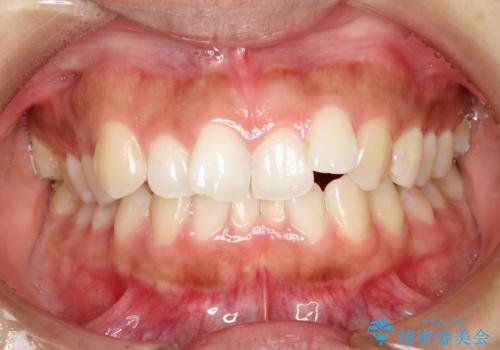

[ インビザライン ]飛び出た前歯を抜かずに矯正治療

担当医 大元洋佑